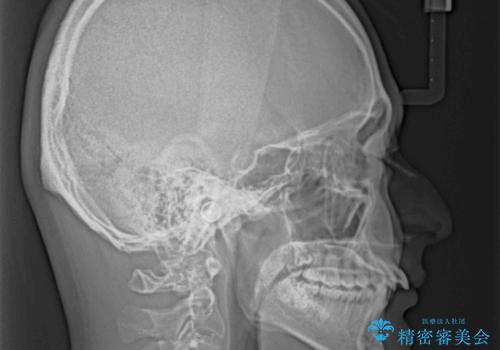

- 深く咬みこんだ前歯と、それに伴い前方に突出した上顎前歯を気にして来院された患者様です。

下顎の歯列は、奥歯が前方に傾斜し、前歯が上顎の歯の付け根に食い込むように内側に傾斜していました。

また、左右の犬歯の位置関係は上顎歯列が前方に位置する咬み合わせとなっており、インビザライン単体で治療するよりは、ワイヤー装置や補助装置を併用した方がより良い仕上がりになることが期待されました。